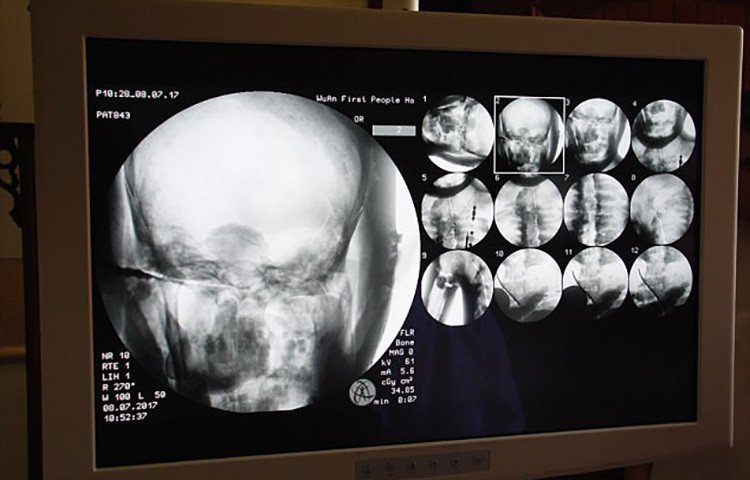

La semana pasada en la provincia de Hebei, al norte de China, un grupo de médicos examinó los restos momificados cubiertos de oro de un maestro budista. Una tomografía computarizada reveló el increíble estado de los órganos del maestro Ci Xian, que se cree murió hace aproximadamente 1.000 años.

Wu Yongqing, unos de los doctores a cargo de la investigación, aseguró que los huesos "están en excelente condición, como los de una persona sana", mientras que el cerebro, su mandíbula superior, dientes, costillas, columna y articulaciones, "se conservan completos".

Medios locales señalan que el "estado natural" del tejido conectivo y las fibras musculares es "muy sorprendente", y subrayan que el análisis de los expertos tiene además un valor cultural y religioso de gran importancia.